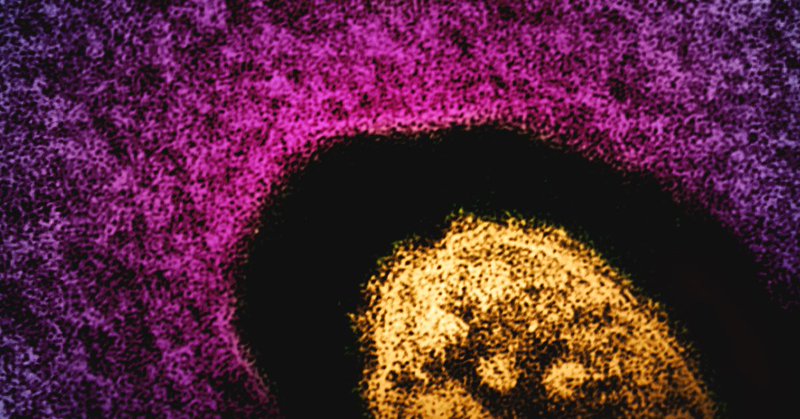

Blood–brain barrier disruption and sustained systemic inflammation in individuals with long COVID-associated cognitive impairment https://t.co/eXUY8ynJYa

nature.com

Nature Neuroscience - Long COVID is a major public health issue since 2020 and exhibits frequent neurological symptoms. Greene et al. propose that brain fog results from leaky brain blood vessels...

Meanwhile, COVID-19 ACTUALLY damages the brain, including the blood-brain barrier. Ongoing brain injury caused by COVID-19 may not always be detected by routine tests https://t.co/62FrXL0h4W

kcl.ac.uk

A new study published recently in Nature Communications details that markers of brain injury are present in the blood many months after COVID-19 infection, despite inflammation blood tests being...